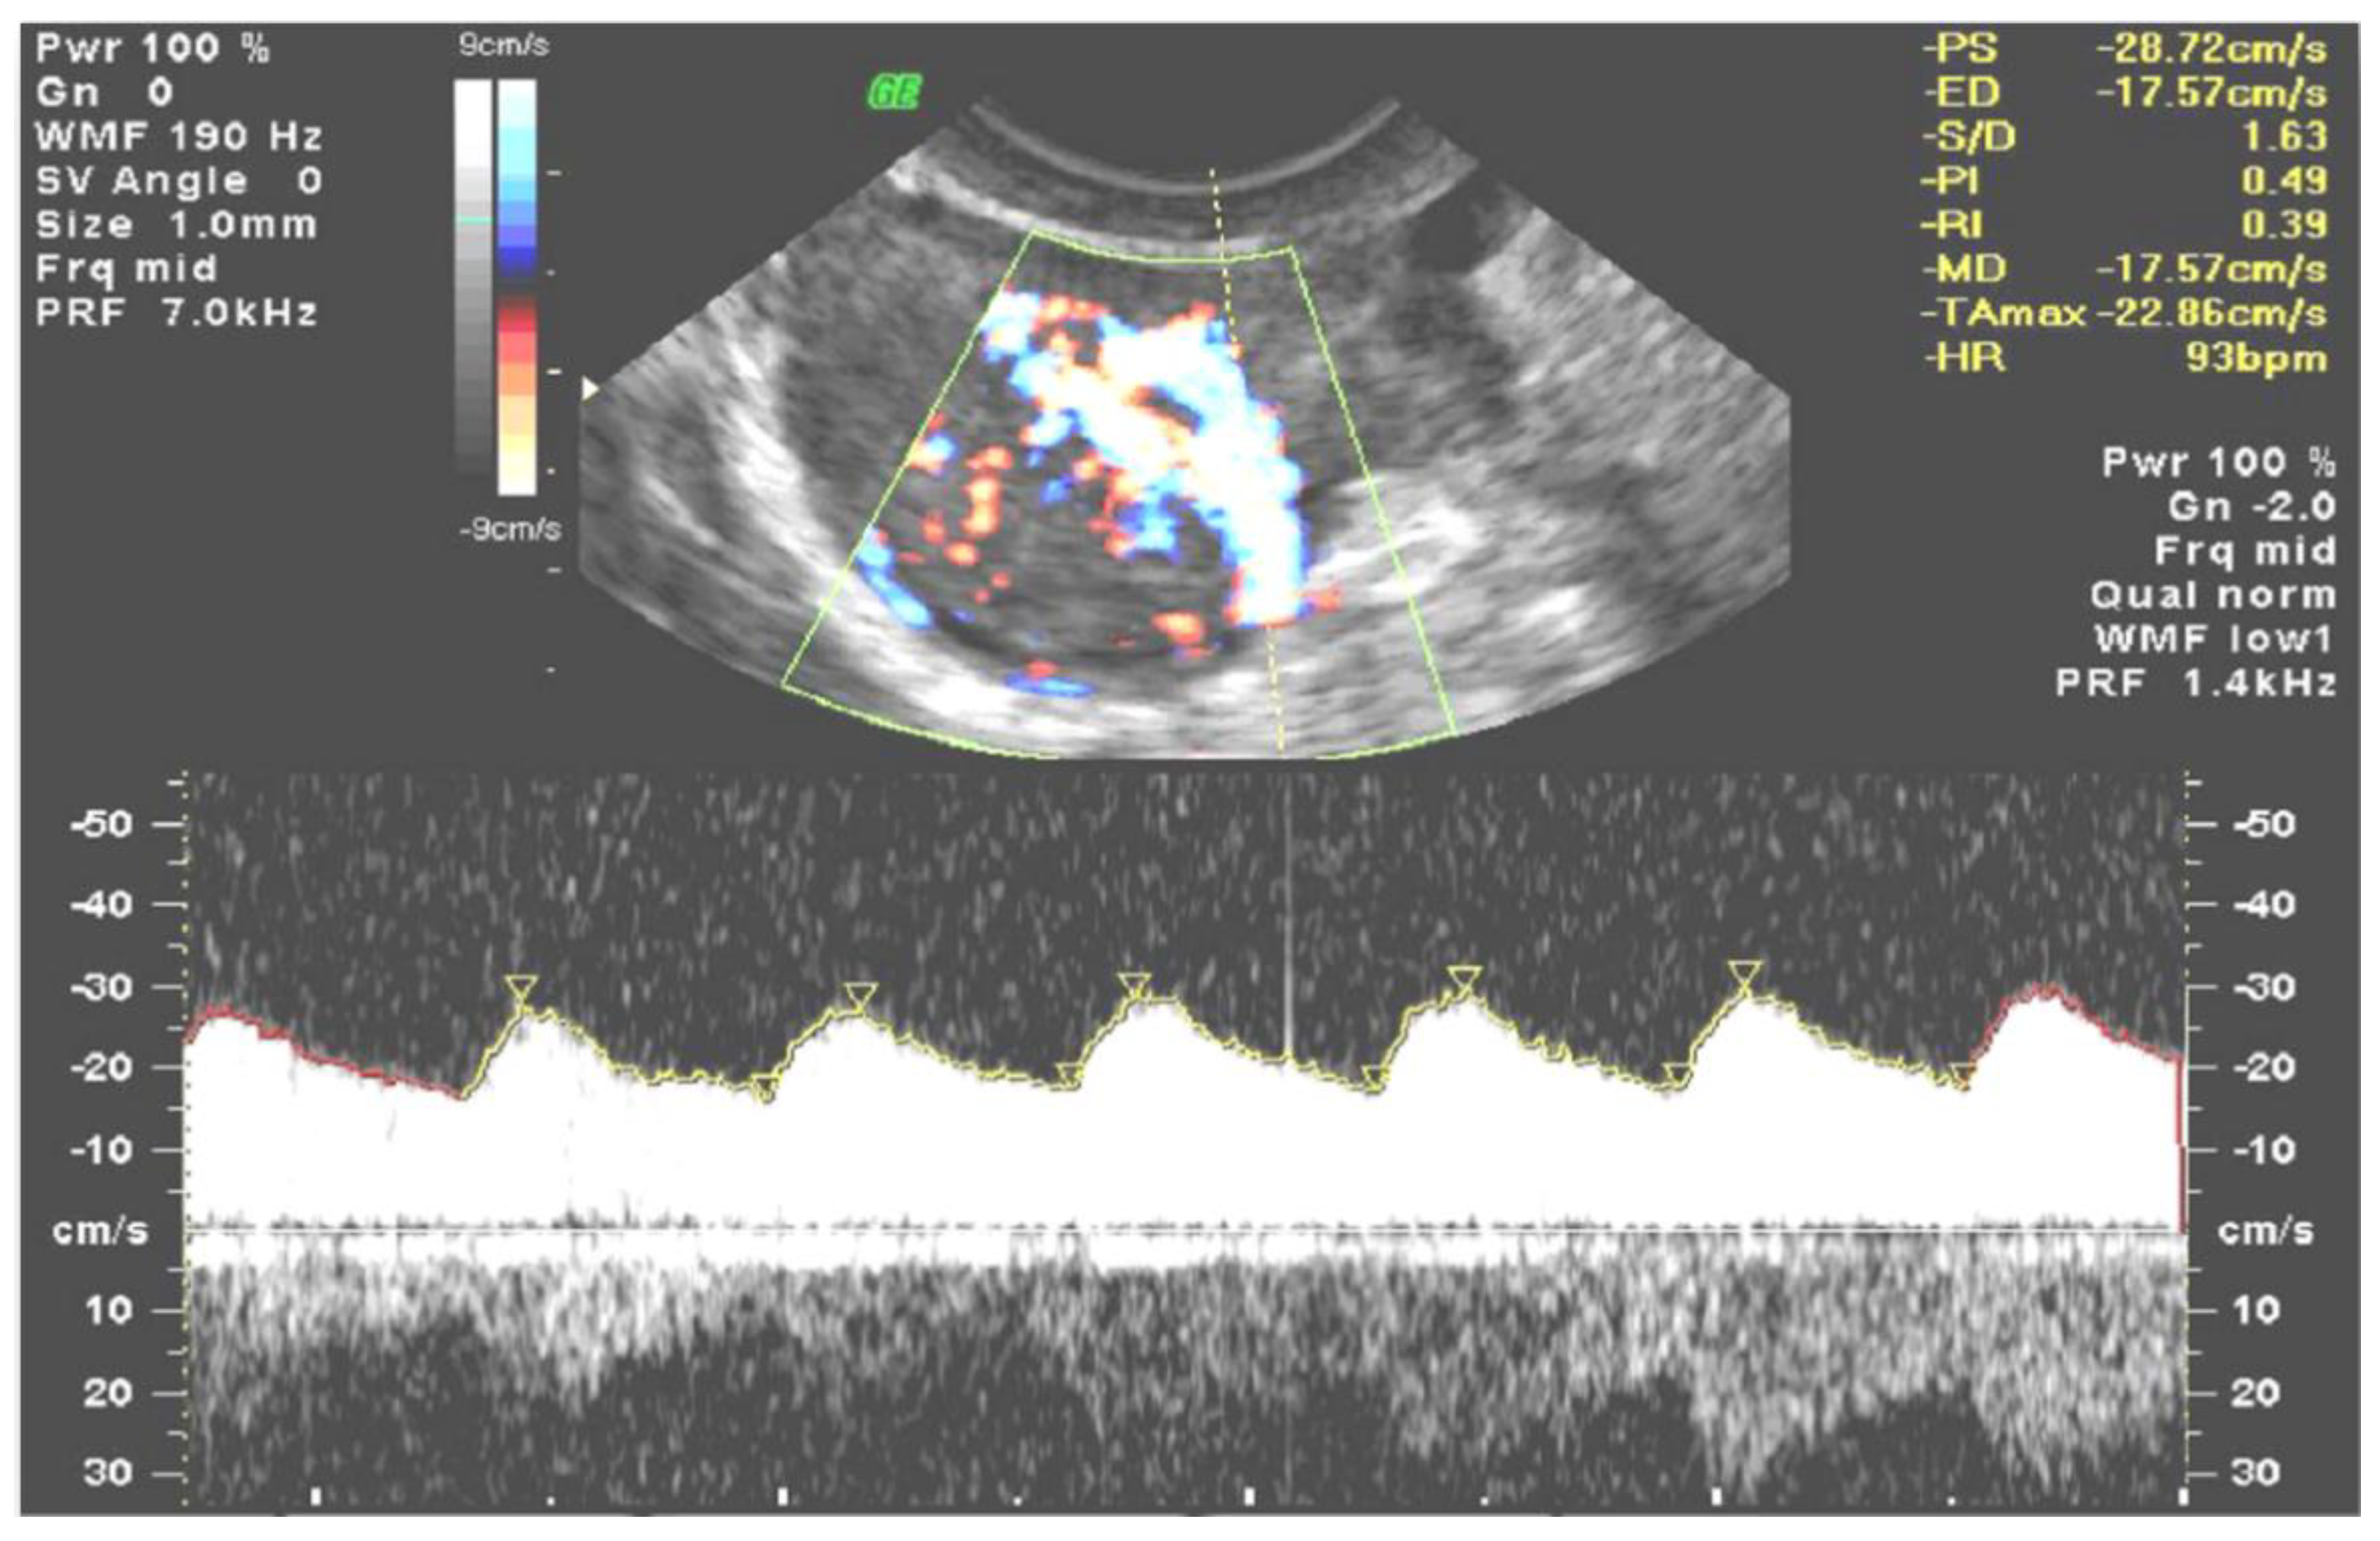

| VIsys * | VIdias * | vS/D + | vPI + | |||||

|---|---|---|---|---|---|---|---|---|

| Mean (%) (SD) | Range | Mean (%) (SD) | Range | Median (IQR) | Range | Median (IQR) | Range | |

| Study group | 53.729 (22.104) | 19.737 to 93.359 | 49.169 (21.827) | 18.508 to 91.800 | 1.096 (0.770) | 1.015 to 1.204 | 0.092 (0.071) | 0.015 to 0.233 |

| Controls | 22.201 (15.989) | 2.876 to 57.912 | 13.447 (11.835) | 1.440 to 38.116 | 1.794 (0.994) | 1.243 to 3.469 | 0.558 (0.581) | 0.182 to 1.105 |